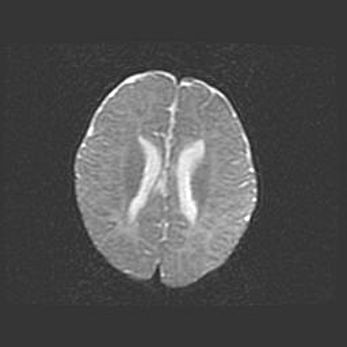

Лейкомаляция с кистозно-глиозной дегенерацией головного мозга.

Возраст: 2 месяца 25 дней

Вес: 6400 г

Окружность головы: 40 см

Срок гестации: 41 неделя

Лейкомаляцию относят к ишемически-гипоксическим повреждениям головного мозга, диагностируемым у новорожденных. При лейкомаляции в головном мозге обнаруживают очаги некроза, возникшие после тяжелой гипоксии и нарушения кровотока. В процессе морфогенеза очаги проходят три стадии: 1) развития некроза, 2) резорбции и 3) формирования глиозного рубца или кисты. Перивентрикулярная лейкомаляция (ПЛ) встречается примерно в 12% случаев среди новорожденных, обычно – у недоношенных детей, причем, частота ее зависит от массы, с которой младенец появился на свет. Наибольшее число малышей страдает лейкомаляцией, если масса при рождении 1500-2500 г.